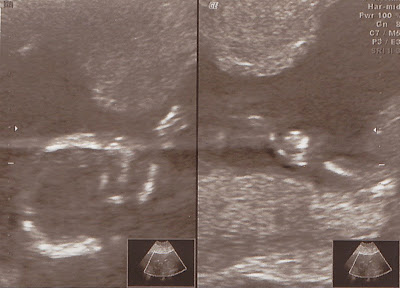

Latest ultrasound photos

soooo the good thing about having an extra cautious doctor is that I get a ton of ultrasounds. I'm now 28 weeks and 5 days, and I will probably have about 3 more. Yay!

Anyway, this ultrasound was done three weeks ago at 25 weeks and 5 days. Our guy weighed 2.3 pounds! Even my doctor was surprised haha. He's gonna be a big boy! So now, he's probably closer to 3 lbs., if not, over 3 lbs. yikes!

Anyway, this ultrasound was done three weeks ago at 25 weeks and 5 days. Our guy weighed 2.3 pounds! Even my doctor was surprised haha. He's gonna be a big boy! So now, he's probably closer to 3 lbs., if not, over 3 lbs. yikes!

DEFINITELY still a boy! Look at that thing!

His little face from the side. The nose isn't quite accurate though. We've seen his nose in 3D and it looks like Aaron's- quite large.

We have our BIG 3D ultrasound tomorrow at three. We'll have video and a ton of 3D photos to share. I'm just excited to see him again!